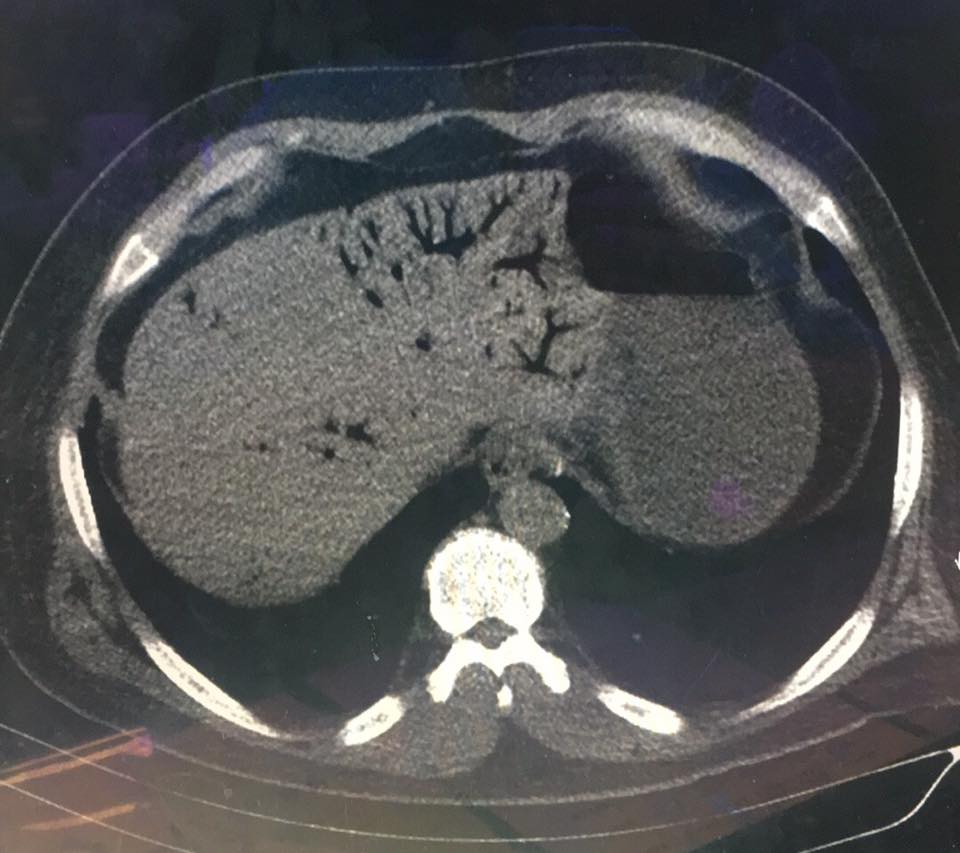

air on a cervical spine radiograph. Pulmonary overinflation injury can cause pneumothorax, requiring aspiration or air or tube thoracostomy. If air enters the pulmonary venous circulation, embolization of the gas through the arterial system occurs. The most sensitive end-organ to such embolization is the brain, and cerebral arterial gas embolism is the term applied to this condition, although the air emboli distribute to other tissues and organs.4 Any neurologic symptom or sign referable to the circulation to the CNS in the setting of barotrauma associated with ascent should be considered to be secondary to cerebral arterial gas embolism. The symptoms, signs, and treatment are discussed below in the section “Arterial Gas Embolism.” Pulmonary barotrauma (Figure 214-1) can occur without a rapid ascent or closed glottis in divers with congenital cysts, obstructive pulmonary disease, or other processes that cause air trapping.